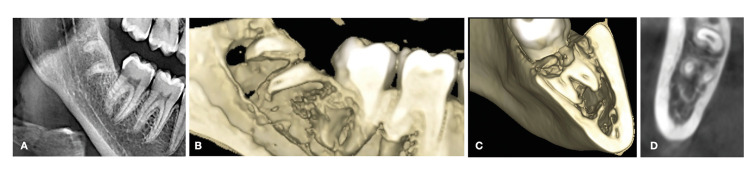

Material and methods: A retrospective case series evaluated the outcomes of coronectomies of impacted mandibular third molars. The inclusion criteria were: available preoperative, immediate postoperative and two-year panoramic radiographs, preoperative cone-beam computed tomography (CBCT), and a complete case history. The clinical evaluation comprised intraoperative complications (mobilized fragments of root and damage to adjacent structures), short-term complications (sensory alterations and postoperative infection), and long-term complications (infection or oral exposure). The IAN position with respect to the roots, root shape, eruption status, third molar position, radicular-complex migration and bone above roots were radiographically evaluated as well.